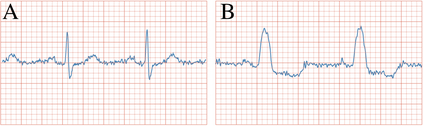

We present $\zeta$-DP, an extension of differential privacy (DP) to complex-valued functions. After introducing the complex Gaussian mechanism, whose properties we characterise in terms of $(\varepsilon, \delta)$-DP and R\'enyi-DP, we present $\zeta$-DP stochastic gradient descent ($\zeta$-DP-SGD), a variant of DP-SGD for training complex-valued neural networks. We experimentally evaluate $\zeta$-DP-SGD on three complex-valued tasks, i.e. electrocardiogram classification, speech classification and magnetic resonance imaging (MRI) reconstruction. Moreover, we provide $\zeta$-DP-SGD benchmarks for a large variety of complex-valued activation functions and on a complex-valued variant of the MNIST dataset. Our experiments demonstrate that DP training of complex-valued neural networks is possible with rigorous privacy guarantees and excellent utility.